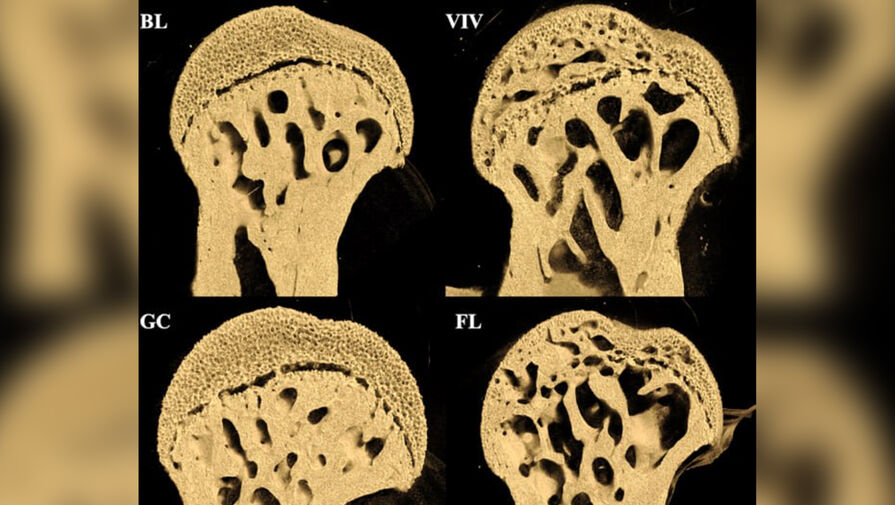

Эксперимент продолжительностью 37 дней показал, что у мышей в космосе значительно пострадали бедренные кости, в то время как поясничный отдел позвоночника остался практически неповрежденным.

Особенно заметные повреждения — крупные отверстия — обнаружились на концах бедренных костей в местах соединения с тазобедренным и коленным суставами.

Исследование опровергло предположение о том, что основную роль в потере костной массы играет космическая радиация. Как выяснилось, повреждения костей развиваются по другому механизму — изнутри наружу, что не характерно для радиационного воздействия.